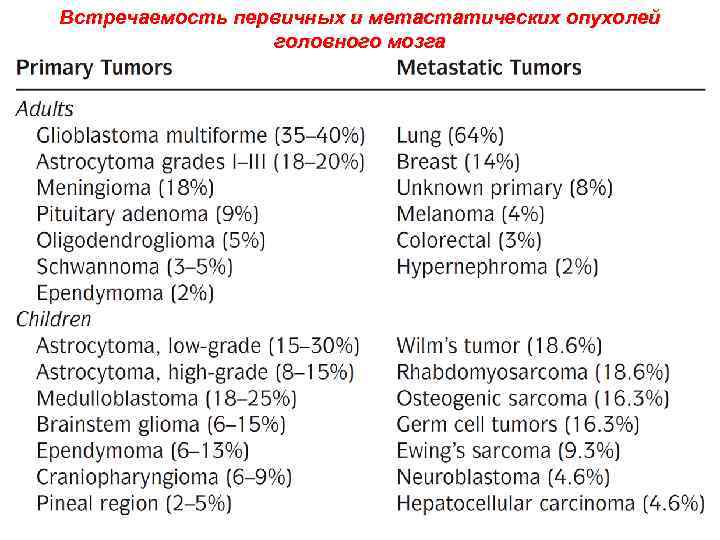

Встречаемость первичных и метастатических опухолей головного мозга 25